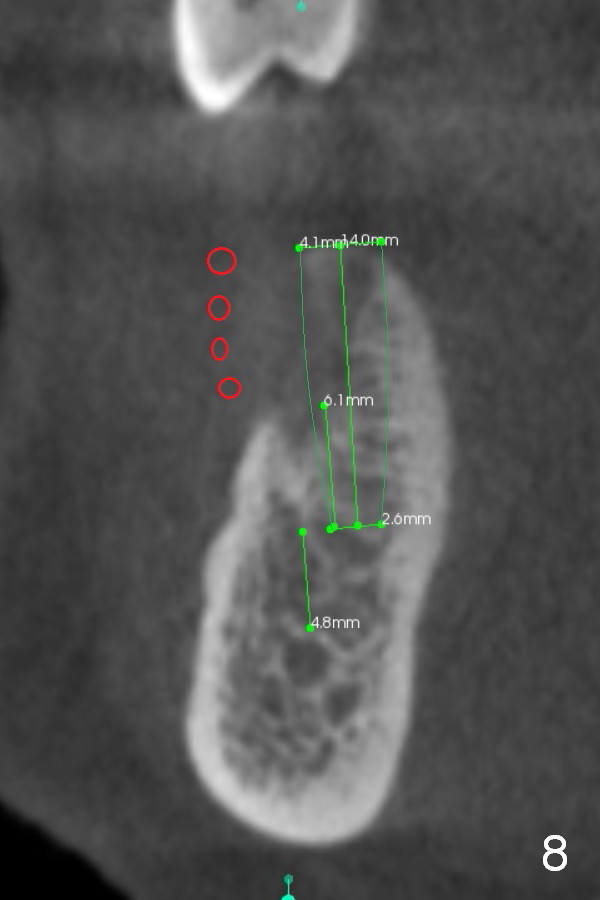

Chief complaint of a 69-year-old lady is "I cannot eat after bottom right bridge removal" (Fig.1). Exam reveals that the tooth #15 is also missing (Fig.2). Four implants are planned. CBCT shows low density of #31 socket (Fig.3,4, bone expanders) and the buccal coronal portion of the #29 socket (Fig.3,6,7, place implant as lingual as possible). The alveolus at the site of #30 is atrophic coronally (Fig.5). If insertion torque of individual implants is reasonably high, an immediate provisional bridge will be fabricated.